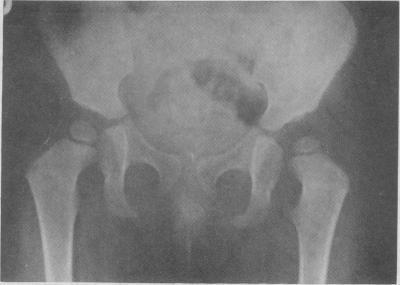

UNTREATED CONGENITAL HIP DISEASE. A STUDY OF THE EPIDEMIOLOGY, NATURAL HISTORY, AND SOCIAL ASPECTS OF THE DISEASE IN A NAVAJO POPULATION.

Am J Public Health Nations Health. 1965 Feb;55(Suppl 2):SUPPL:1-44.